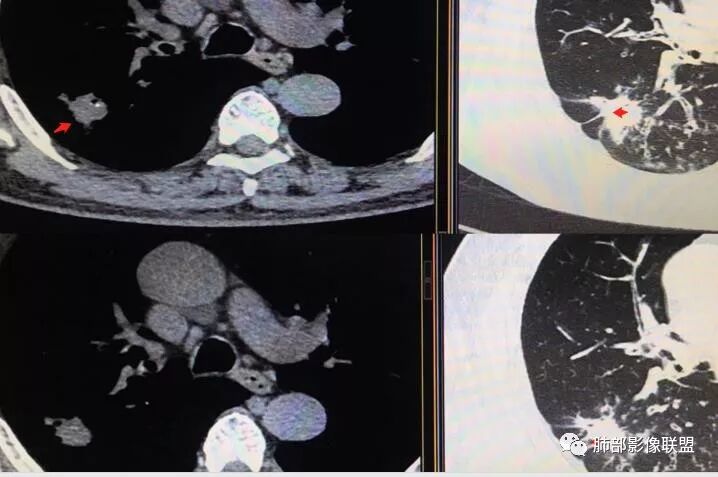

胸CT示病变位于右肺上叶,右肺上叶前段支气管壁不规则增厚狭窄、远端扩张。右肺上叶后段实变影,纵隔窗实变内可见钙化灶,可见支气管引流征,引流支气管壁明显增厚,边缘可见短硬毛刺,胸膜牵拉,u型征,周围可见卫星灶,并可见支气管扩张及其管壁增厚;病灶整体存在膨胀性生长。考虑良性病(结核)变基础上合并癌变,腺癌?

老年男性,咳嗽半年,右肺上叶后段实性结节伴粟粒状卫星灶,结节内有钙化,部分边缘平直,周围见长索条,有胸膜牵拉,结核是明确的,常规需要增强判断有无合并肺癌,当然该患者已经穿刺。

钙化与软组织成分明显不成比例时一定要小心ca,尤其钙化位于偏心的位置时,肿瘤包裹钙化。

3.本例病灶影像表现为:右肺上叶后段不规则结节灶,病灶整体存在膨胀性生长,可见毛刺、胸膜牵拉、分叶及钙化征象,近心端小空洞,周围见点片状卫星灶并出现磨玻璃影,近端支气管壁增厚,管腔扩张,既有恶性征象,也有结核的征象。南边老师考虑结核与腺癌同时存在,但遗憾的是缺乏增强扫描图像,亦未提供结核相关辅助检查结果。